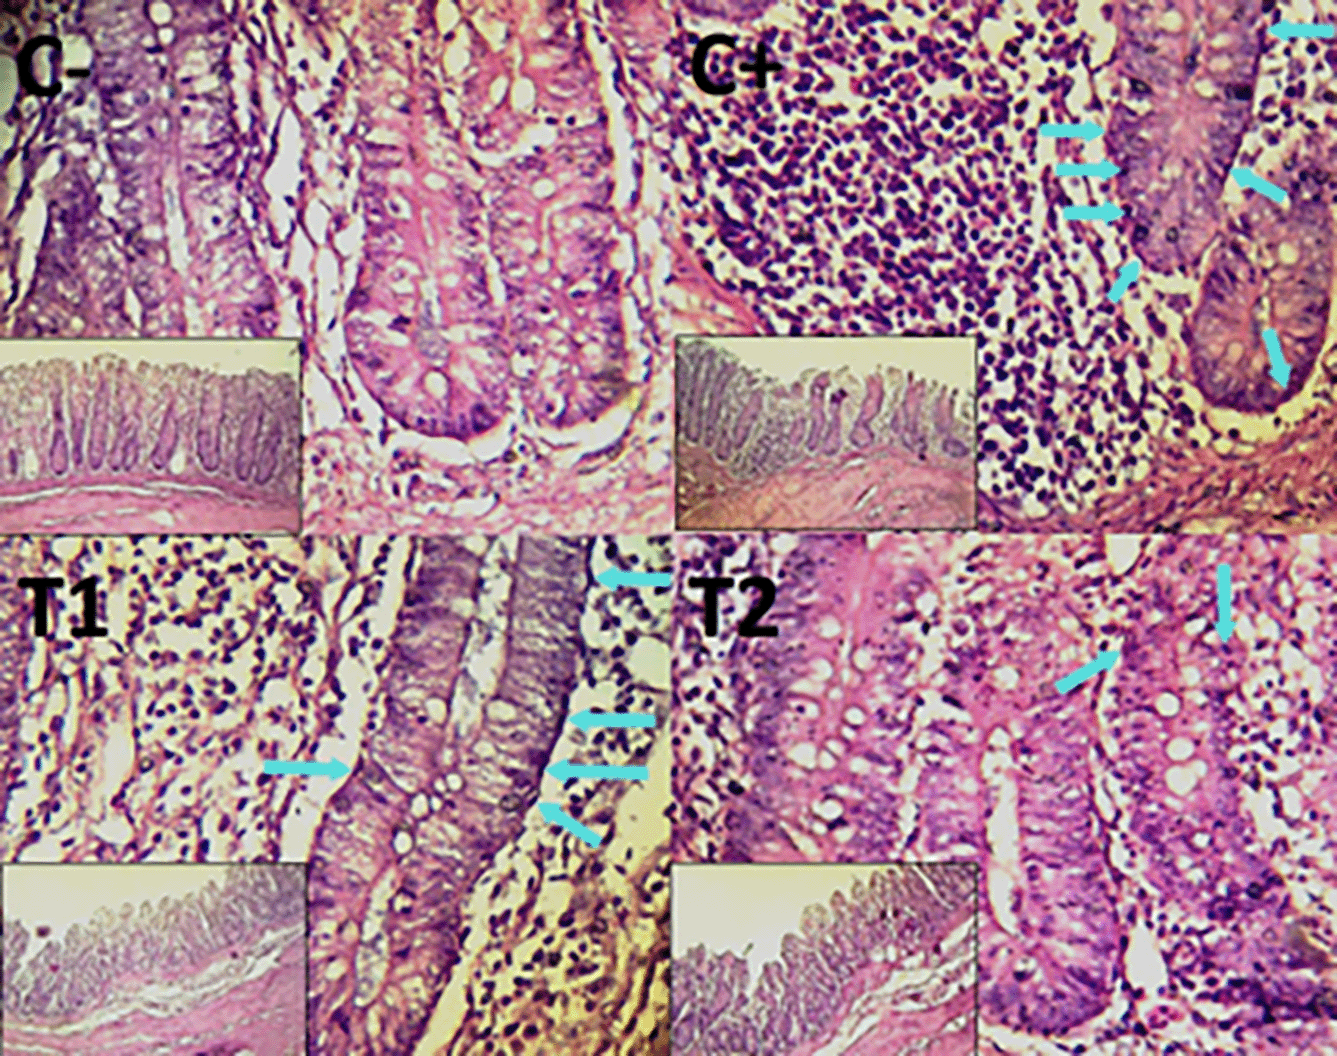

The findings of the scoring analysis of the broiler chickens’ mucosal rupture, necrosis, and hemorrhage in the cecum ( Table 2) and colon ( Table 3). The control group, treatment group C-, had the lowest mean rank. The C+ treatment group, which received a combination of mycotoxin at 0.1 mg/kg feed doses of ochratoxin A and aflatoxin B1, had the highest mean rank. The T1 treatment group received a combination of mycotoxin (0.1 mg/kg feed of aflatoxin B1 and ochratoxin A) and mycotoxin binder agent (1.1 g/kg feed) at each dose. Treatment group T2 received a combination of mycotoxin (0.1 mg/kg feed containing aflatoxin B1 and ochratoxin A) and mycotoxin binder agent (1.6 g/kg feed) as indicated in Table 2. Furthermore, the T2 group demonstrated a progressive improvement in the histological differences related to mucosal rupture, hemorrhage, and necrosis in the cecum organ ( Figures 2–4).

The control group, treatment group C-, had the lowest mean rank. Treatment group C+, which received a combination mycotoxin dose of 0.1 mg/kg feed containing both ochratoxin A and aflatoxin B1, had the highest mean rank. The T1 treatment group received a combination of mycotoxin (0.1 mg/kg feed) and mycotoxin binder agent (1.1 g/kg feed) at each dose of aflatoxin B1 and ochratoxin A. Table 3 shows that the T2 treatment group received a combination of mycotoxin (0.1 mg/kg feed containing each of the compounds aflatoxin B1 and ochratoxin A) and mycotoxin binder agent (1.6 g/kg feed). The T2 group demonstrated a progressive improvement in the histological differences of mucosal rupture, haemorrhage, and necrosis in the colon organ ( Figures 5–7).